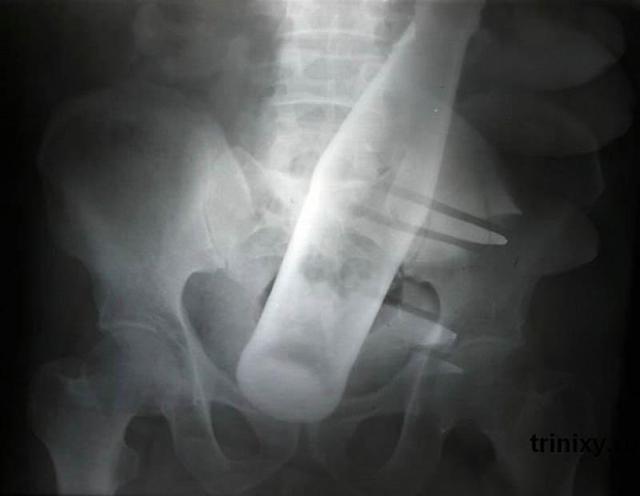

Бутылка из-под «Пепси» в анусе 60-летнего мужчины.